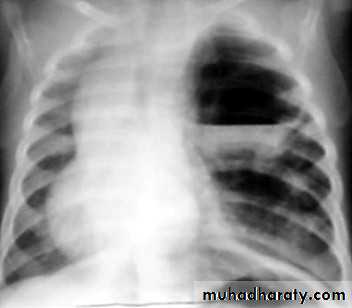

Total collapse total consolidation

Total collapse

48.opasified hemi thorax

49.total collapse

50.pleural effusion